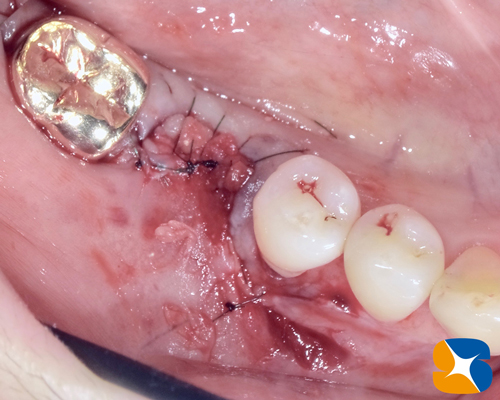

いざ歯肉を切開してみると大きく欠落していた骨が見事に再生(硬度のある骨)されていました。

骨の状態も硬くて良好。インプラント施術も無事に完了いたしました。

インプラントの周囲に固い歯肉で囲まれるように血液から製作したCGF の粘膜を敷き詰めました。

使用した糸はマイクロスコープで確認しながら、眼科用の極細糸で優しく丁寧に縫いました。

ノーベルバイオケア社:アクティブ直径4.3㎜。高さ10㎜。および On1 ベースアバットを設置。